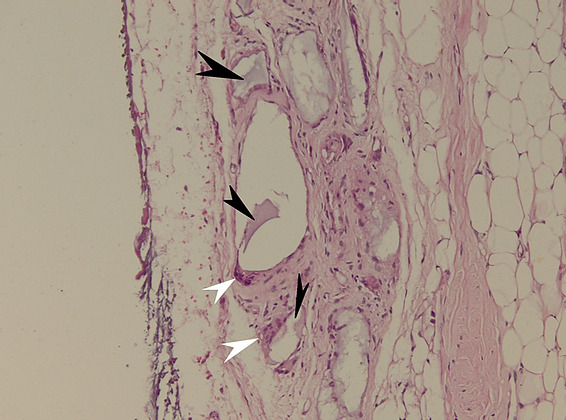

The histolopathological analysis performed shows in the meshes of the prosthetic material, fibrovascular tissue and minimal polymorphic inflammatory infiltrate (lymphocytes, plasma cells and polymorphonuclear neutrophils) and moderately frequent multinucleated giant cells of the “foreign body” type at the interface with the hydroxyapatite as well as osteoclasts at the interface with the hydroxyapatite nanocomposite material. At different levels in the muscle tissue and in the corresponding sclera, amorphous, acellular material (mono and multifilament surgical threads) bordered by multinucleated giant cells of the “foreign body” type is observed. (Figure 11,12). It can be observed that the invasion of the implant with fibrovascular material begins from the incision and the initial suture area, and the presence of multinucleated giant cells of the foreign body type in not very large numbers attests to good compatibility, at least equal to that of the suture material.

Figure 11: Histopathological appearance of the hydroxyapatite implant in hematoxylin-eosin (HE) staining – subject 1. The following structures are depicted: black arrow – striated muscle, white arrow – remnant sclera, empty arrow – incision site, arrowhead – surgical threads. Proliferation of fibrovascular tissue is observed inside the implant starting from the incision and suture site with uniform distribution through the nanostructured hydroxyapatite material (observed as white-gray areas marked by blue arrows). The fibrovascular tissue present attests to the complete vascularization of the implant 2 months after implantation with good tolerability.